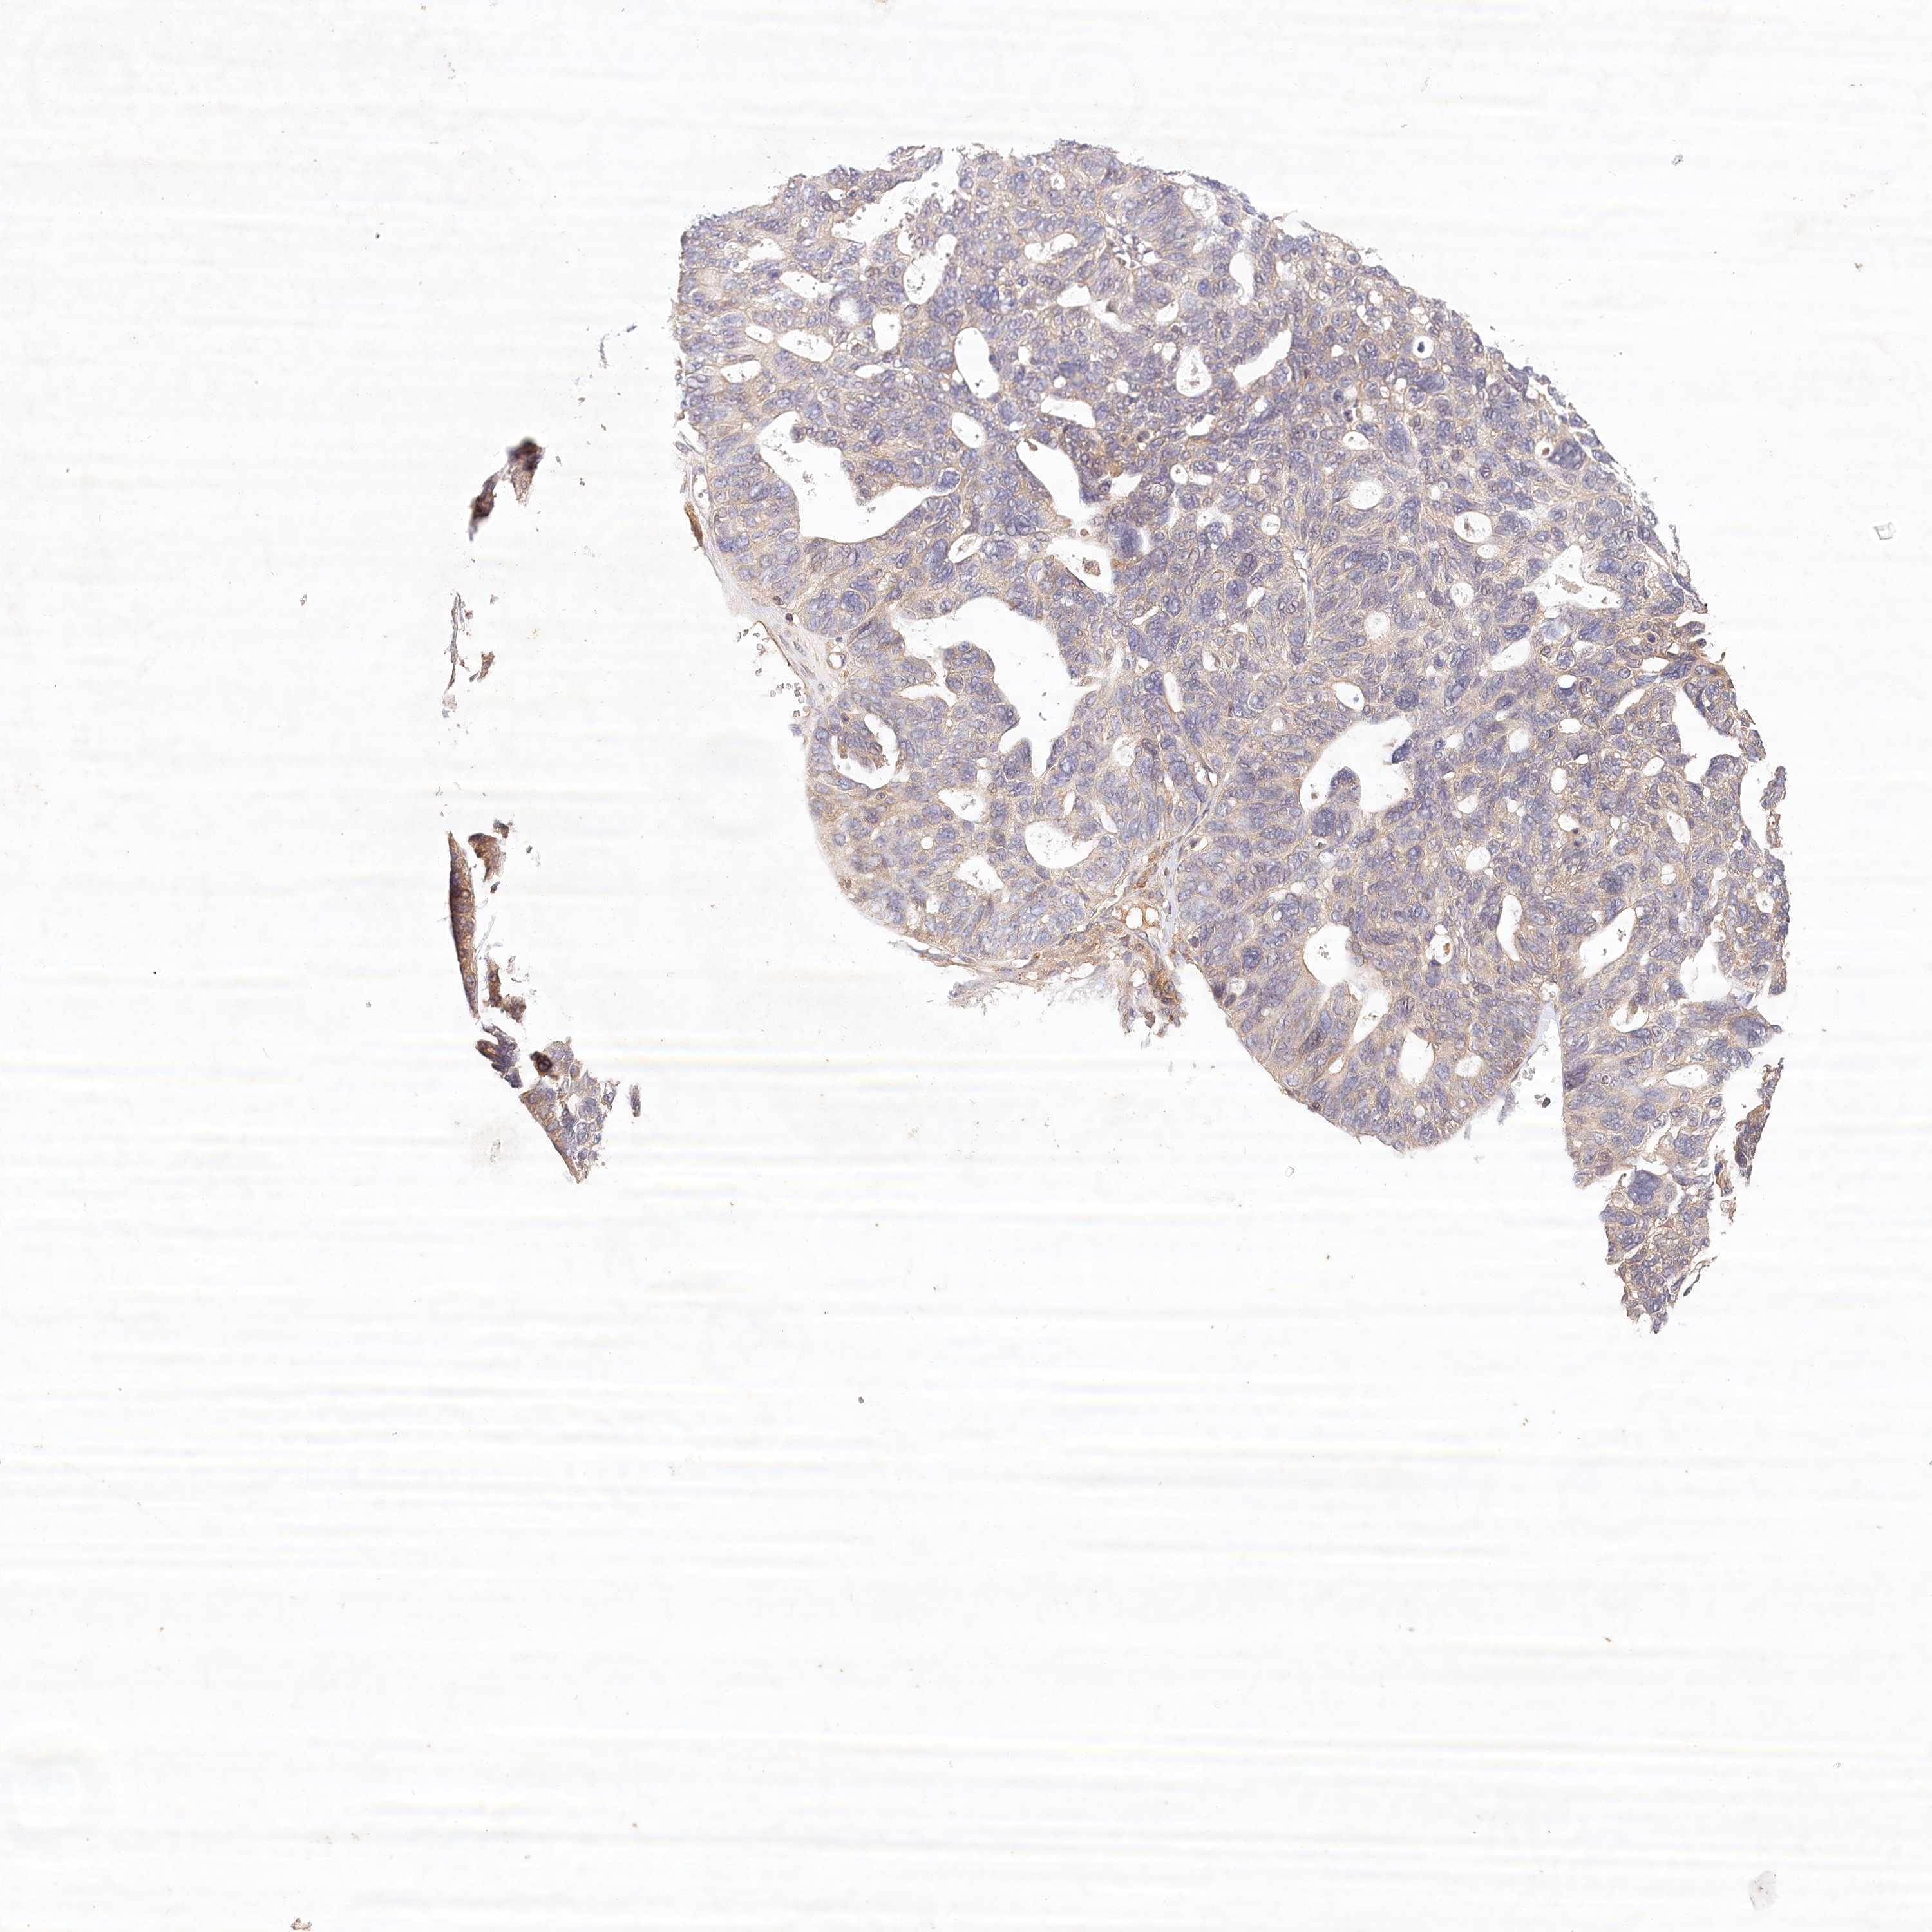

OVARIAN CANCER - Protein expressioni

A mouse-over function shows sample information and annotation data. Click on an image to view it in a full screen mode. Samples can be filtered based on level of antibody staining by selecting one or several of the following categories: high, medium, low and not detected. The assay and annotation is described here.

Note that samples used for immunohistochemistry by the Human Protein Atlas do not correspond to samples in the TCGA dataset.

Antibody stainingi

Antibody staining in the annotated cell types in the current human tissue is reported as not detected, low, medium, or high, based on conventional immunohistochemistry profiling in selected tissues. This score is based on the combination of the staining intensity and fraction of stained cells.

Each image is clickable and will lead to virtual microscopy that enables deeper exploration of all samples and also displays staining intensity scores, fraction scores and subcellular localization as well as patient and tissue information for each sample.

Antibody HPA032060

Antibody HPA032062

Antibody CAB034116

Staining

High

Medium

Low

Not detected

Intensity

Strong

Moderate

Weak

Negative

Quantity

>75%

75%-25%

<25%

None

Location

Nuclear

Cytoplasmic/membranous

Cytoplasmic/membranous,nuclear

Cystadenocarcinoma, serous, NOS

Carcinoma, endometroid

Cystadenocarcinoma, mucinous, NOS

Carcinoma, NOS